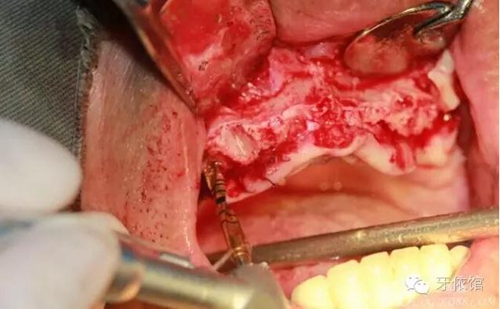

右上5,6,7牙位內(nèi)提升

切牙壓孔內(nèi)植入植體,扭力50n

將前牙區(qū)取下的骨粉碎

將粉碎的骨填入上頜竇內(nèi)(未加骨粉,全部自體骨)